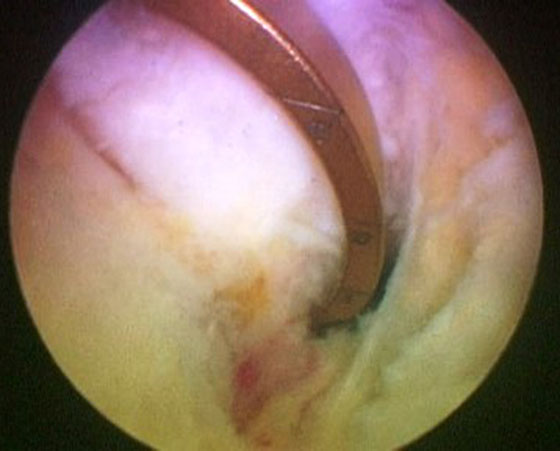

Se procede luego a realizar el portal posterointerno. Dado que no se reseca el remanente HPM, el espacio para acceder a la cápsula posterointerna se encuentra reducido, para ampliarlo realizamos una mínima “notchplastia” en la parte posterior del cóndilo interno (Fig. 4). Con la visión desde el portal anterointerno colocamos un switcher, de los utilizados en cirugía de hombro, desde el portal anterolateral ubicándolo entre el remanente ligamentario y el cóndilo interno (Fig. 5). Luego se pasa la cánula de irrigación guiada por el switcher y se accede con la óptica a la cápsula posterointerna, bajo visión directa colocamos una aguja espinal para localizar el portal, completando con bisturí para luego colocar la cánula de trabajo (Fig. 6). En este punto se vuelve a pasar el artroscopio al portal anterointerno, se introduce el shaver por la cánula del portal posterointerno, y se realiza la limpieza de la capsula posterior, siempre con la hoja de corte hacia anterior para evitar la lesión de estructuras vasculonerviosas. Se continúa alternando los portales anterointerno y posterointerno con visión, shaver, pinza basket y raspas de 90º, hasta completar la desinserción de cápsula posterior e identificar el remanente distal del ligamento sin afectar la inserción. En los casos en que la lesión ha sido en la sustancia colocamos la guía tibial distal a la inserción tibial (Fig. 7). Si la lesión ha comprometido la inserción tibial, levantamos la cicatriz que encontremos y colocamos la guía por debajo del remanente (Fig. 8). Para la introducción de la guía sin lesionar los remanentes ni el LCA se coloca la óptica en el portal anteroexterno y se controla el ingreso de la guía por el espacio entre el remanente y el cóndilo interno (Fig. 9). Se pasa el clavo guía, siempre cuidando de llegar en forma motorizada hasta contactar la cortical posterior y se completa el pasaje golpeando con martillo para evitar una salida brusca del mismo. Se pasa la fresa canulada del diámetro adecuado, protegiendo la emergencia de la misma con una cureta. Una vez completado el túnel tibial, se pasa un alambre o cable desde el orificio externo tibial hacia proximal, con visión en portal posterointerno, al ver emerger el alambre o cable por el orificio tibial posterior, se vuelve la óptica al portal anterointerno para controlar el pasaje de un grasper desde anteroexterno a través del intervalo entre HAL y LCA, y dirigirlo hacia posterior (Fig. 10); se vuelve con la óptica al portal posterointerno y se visualiza la recuperación del alambre o cable con el grasper hacia la parte anterior de la rodilla (Fig. 11). Se amplía el portal anteroexterno y se anuda la sutura tractora del injerto al alambre o cable, y traccionando desde el orificio distal del túnel tibial se hace ingresar el injerto en forma retrógrada a la articulación y, luego, al túnel tibial por su orificio posterior. En caso que se utilice el injerto de tendón cuadricipital la parte tendinosa irá al túnel tibial y el bloque óseo al femoral. Una vez ingresado el injerto al túnel tibial, se vuelve la óptica al portal anterointerno, en el portal anteroexterno tendremos la sutura tractora del extremo “femoral del injerto”, es aconsejable en este punto llevar el injerto lo más distal posible para tener mejor visión articular, enhebrar la sutura tractora en una cánula de unos 6 mm de diámetro, para asegurarse que la sutura tractora y la clavija pasasutura pasan por el mismo espacio sin incluir tejido sinovial o grasa retrorrotuliana (Fig. 12). Se procede a pasar la aguja pasasutura por el túnel femoral, saliendo por las partes blandas de la parte medial de la rodilla, se tracciona y se asciende el injerto colocándolo en el túnel femoral. En caso que el injerto tenga bloque óseo puede ser necesario redirigir el mismo para ubicarlo en el túnel femoral, para esto ubicamos la visión en el portal anteroexterno y por el portal anterointerno utilizamos el trocar romo o el palpador para realizar una polea y mejorar la tracción para que ingrese el taco óseo en el túnel femoral (Fig. 13). Luego se realiza la fijación femoral con tornillo de interferencia de titanio o biodegradable. A continuación liberamos el manguito neumático, porque creemos que produce un espasmo en los isquiotibiales que dificulta la reducción de la tibia, dejamos pasar unos minutos que utilizamos para colocar un tornillo maleolar con arandela, distal al orificio externo del túnel tibial para realizar una segunda fijación de la parte tibial. Preferimos hacerlo antes de colocar el tornillo interferencial, porque esto generará una presión hacia posterior de la tibia. Se realiza la reducción tibial en 90° de flexión de la rodilla, se tracciona del injerto y se coloca el tornillo de interferencia tibial, luego la sutura remanente (polyester 5) se anuda en el tornillo maleolar completando la 2da fijación. Por último se constata con una nueva visión articular la posición y tensión del injerto (Fig. 14).

Figura 4